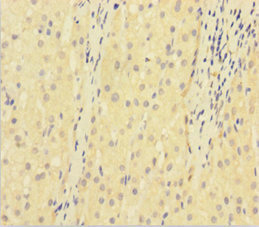

Immunohistochemistry of paraffin-embedded human lung cancer using CSB-PA07279A0Rb at dilution of 1:100